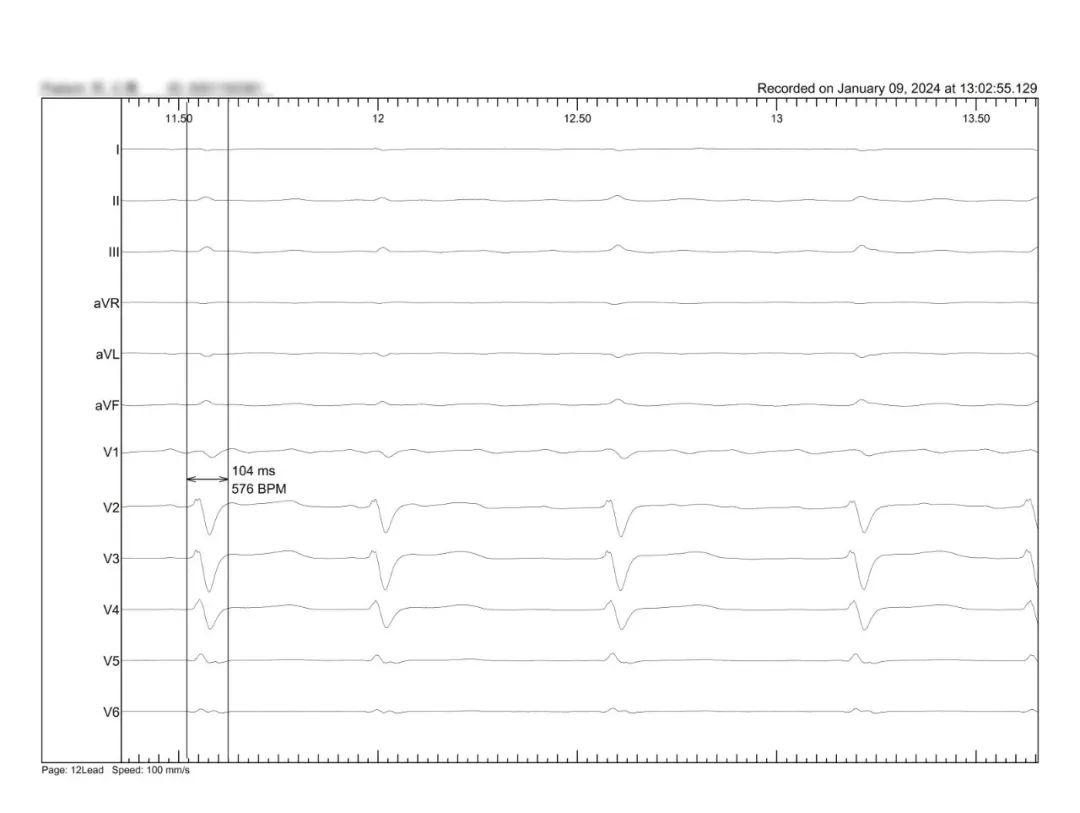

术前患者自身心电图LBBB,QRS宽度168ms

HBP起搏后高输出纠正LBBB

最终融合QRS

LBBB患者术前